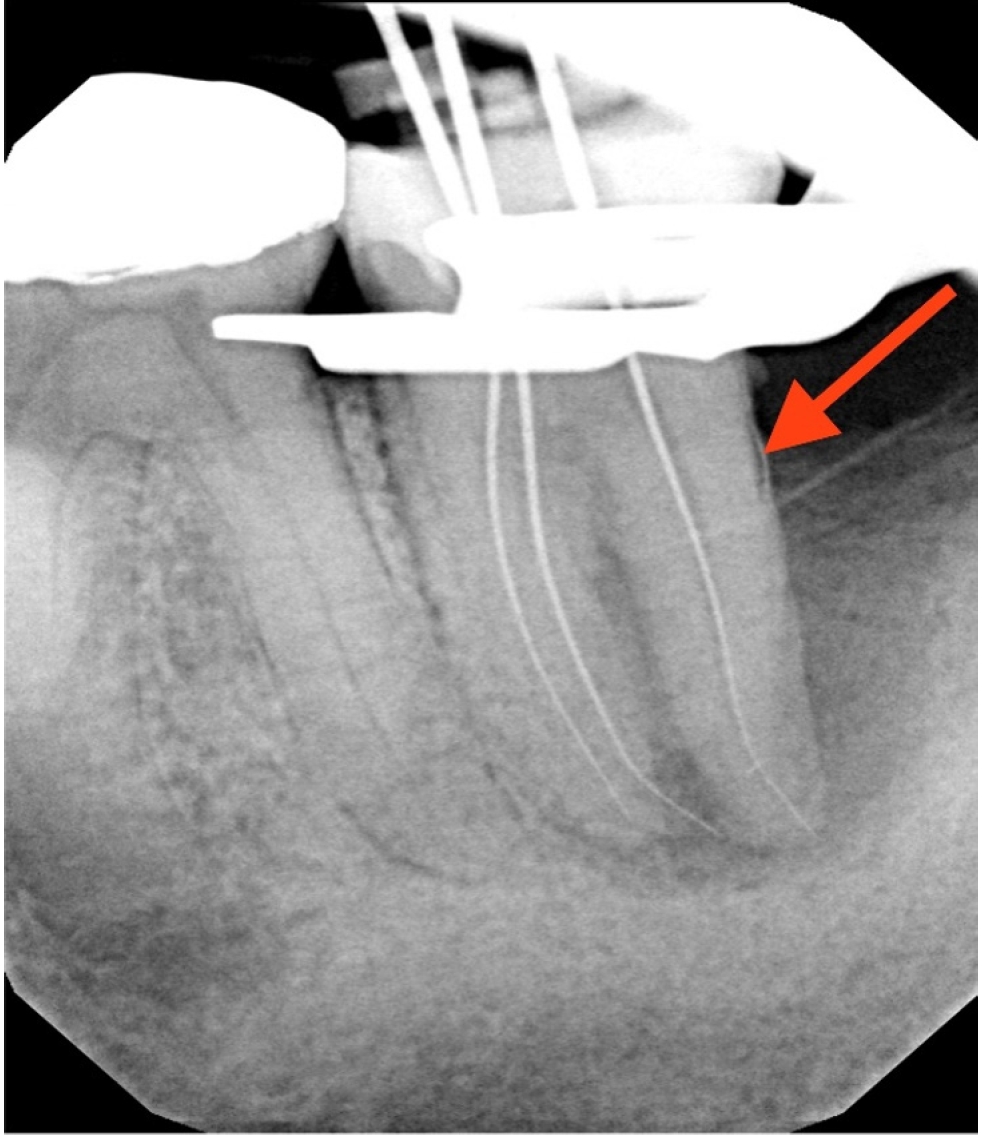

Working lengths were determined using an electronic apex locator (RootZX; J Morita, Kyoto, Japan) and confirmed with a periapical radiograph, which also showed a radiopaque fragment consistent with a cemental tear (Figure 2). The chamber was flooded with 5% sodium hypochlorite, and the canals were instrumented using size 8, 10, 15, and 20 K files, followed by a 25/.07 Primary Wave One Gold (Dentsply Sirona, Charlotte, NC, USA) reciprocating file. Irrigation was performed with 12 mL of 5% sodium hypochlorite with ultrasonic activation for 30 seconds per canal. Calcium hydroxide was placed as an intracanal medicament with a lentulo spiral, and the tooth was temporized with a sterile sponge and Cavit (3M ESPE, St. Paul, MN, USA). The patient was informed to return in 2 weeks for completion of the root canal.

Figure 2.

Working length radiograph showing radiopaque fragment consistent with a cemental tear along distal root (red arrow).

Figure 2. Working length radiograph showing radiopaque fragment consistent with a cemental tear along distal root (red arrow).